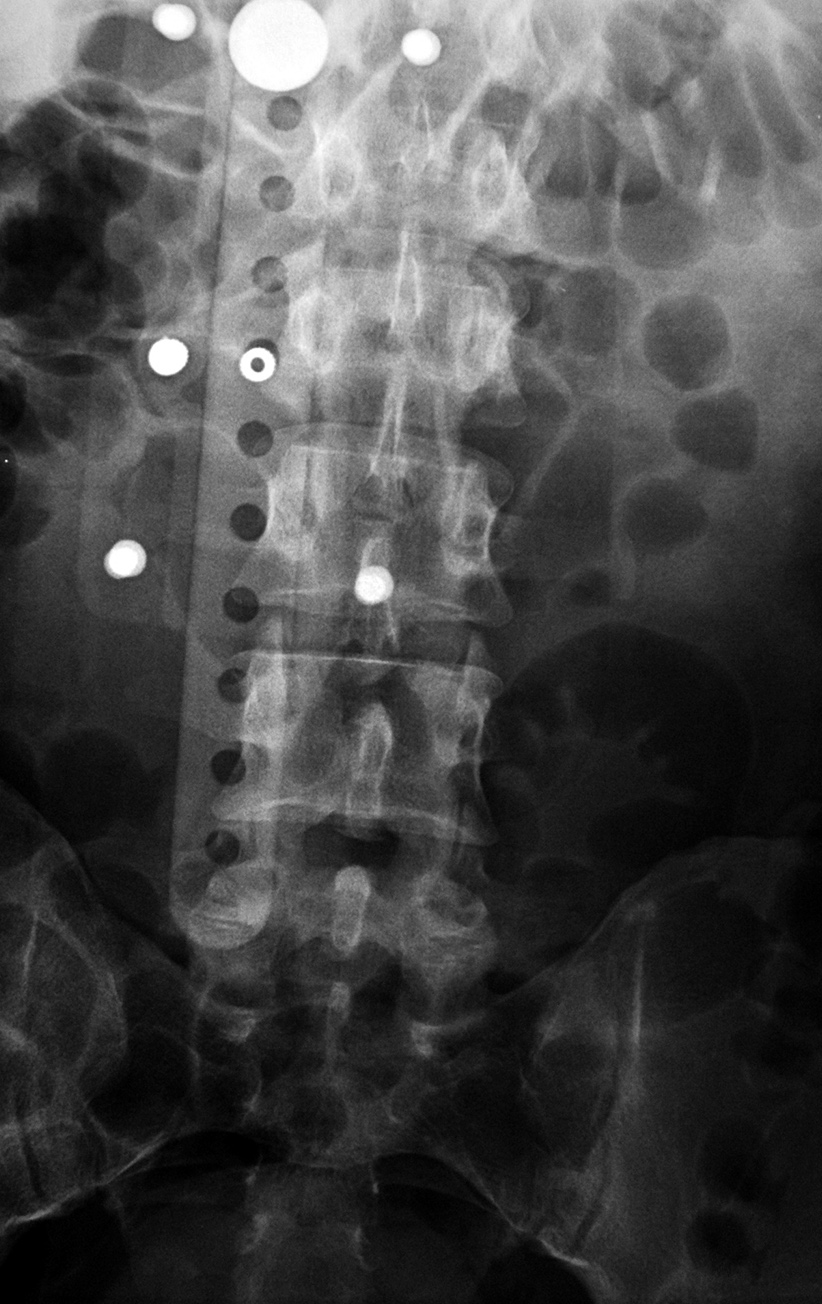

| TLSO (Boston) brace AP view |

TLSO (Boston) brace lateral view |

| This brace was used to treat an L1 compression fracture |